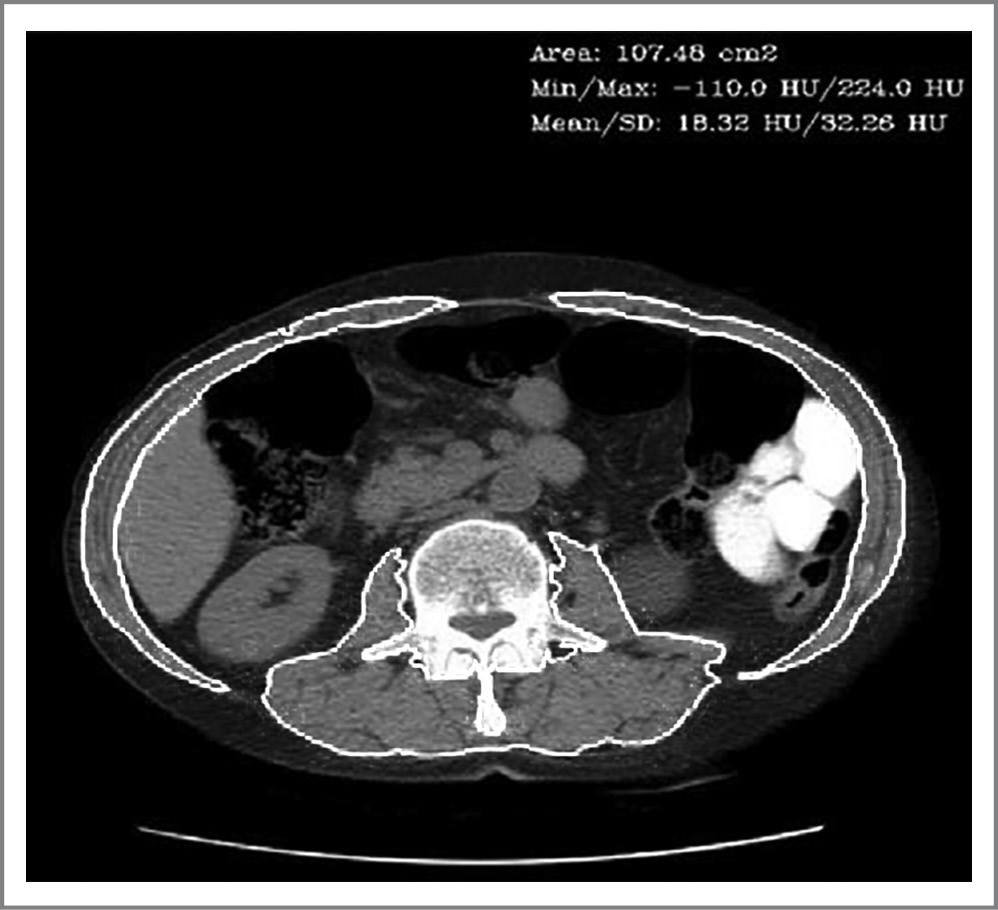

Программный модуль в настоящий момент с КТ-снимками на уровне LIII позвонка производит автоматическую сегментацию мышечной ткани; определяет площадь области интереса, а также минимальных, максимальных и средних значений области интереса в единицах шкалы Хаунсфилда (Hounsfield units – HU); визуализирует контуры мышечной ткани поверх исходных снимков и наносит необходимые значения (рис. 2).

Рис. 2. Аксиальный КТ-срез. Kонтуры мышечной ткани поверх исходных снимков.

Fig. 2. Axial computed tomography slice. Muscle tissue contours over of the original images.